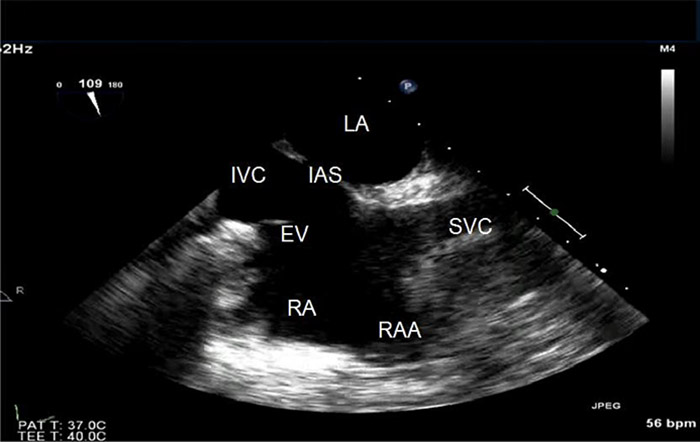

Both transthoracic echo (TTE) and transesophageal echo (TEE) have been used for the diagnosis and assessment of PFO. TTE is the preferred diagnostic test of choice, given its less invasive nature. TEE, while more invasive, gives better visualization of the atrial septum resulting in greater sensitivity in making the diagnosis. As a result, TEE is usually reserved for divers where there is a very high index of suspicion for PFO but the TTE was inconclusive.

A bubble study is where two syringes of normal saline solution are flushed back and forth into each other via a stopcock to produce very small bubbles in the solution (called “agitated saline”) and then this solution is injected into an arm vein of the subject A bubble study increases the diagnostic sensitivity of a PFO by enhancing echocardiographic detection of the intermittent right-to-left shunting across a typical PFO and should always be performed in divers when PFO is a concern. Agitated saline contrast injected intravenously during Valsalva maneuver with release of straining when contrast is visualized in the right atrium increases sensitivity. Visualization of contrast microbubbles passing from the right to left atrium through the visualized foramen ovale during the release phase is diagnostic of an interatrial communication. In clinical practice, the actual site of right-to-left shunting may not be convincingly visualized or recorded for technical reasons. If a recording convincingly demonstrates microbubbles appearing in the left atrium immediately after arriving in the right atrium, then the presence of a PFO can be presumed. If bubbles appear in the left atrium > 5 beats after they appear in the right atrium, then the possibility of anomalous pulmonary arteriovenous connection to the left atrium or pulmonary arteriovenous malformations must be considered.

Contrast injected through an upper extremity vein may be washed away by contrast-free blood flow from the inferior vena cava directed by the Eustachian valve, creating a false-negative result (12). Injection of contrast via the femoral vein has been proposed to enhance detection by TEE, with the streaming effect of directed inferior vena cava flow to the region of the fossa ovalis and through a patent foramen (13). However, starting a femoral vein IV in the groin of a subject is not usually a practical option.